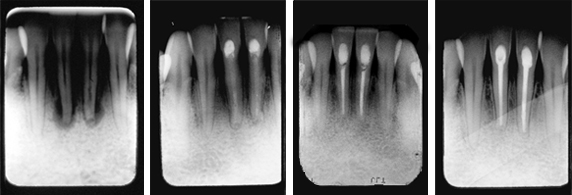

Treatment of Abscessed Teeth

Four months after an auto accident in which the patient’s chin hit the steering wheel, the patient presented with loose and painful lower central incisors. We immediately performed root canals and placed TempCanal in the canals to stimulate healing.

Fig. 1: Radiograph showing abscessed teeth with considerable bone loss.

Fig. 2: Six months after root canals and treatment with TempCanal, radiograph shows bone filling in and healing occurring.

Fig. 3: One year follow up shows healing and obturation with Pulpdent Root Canal Sealer.

Fig. 4: Radiograph taken nine years after final filling shows long term success.